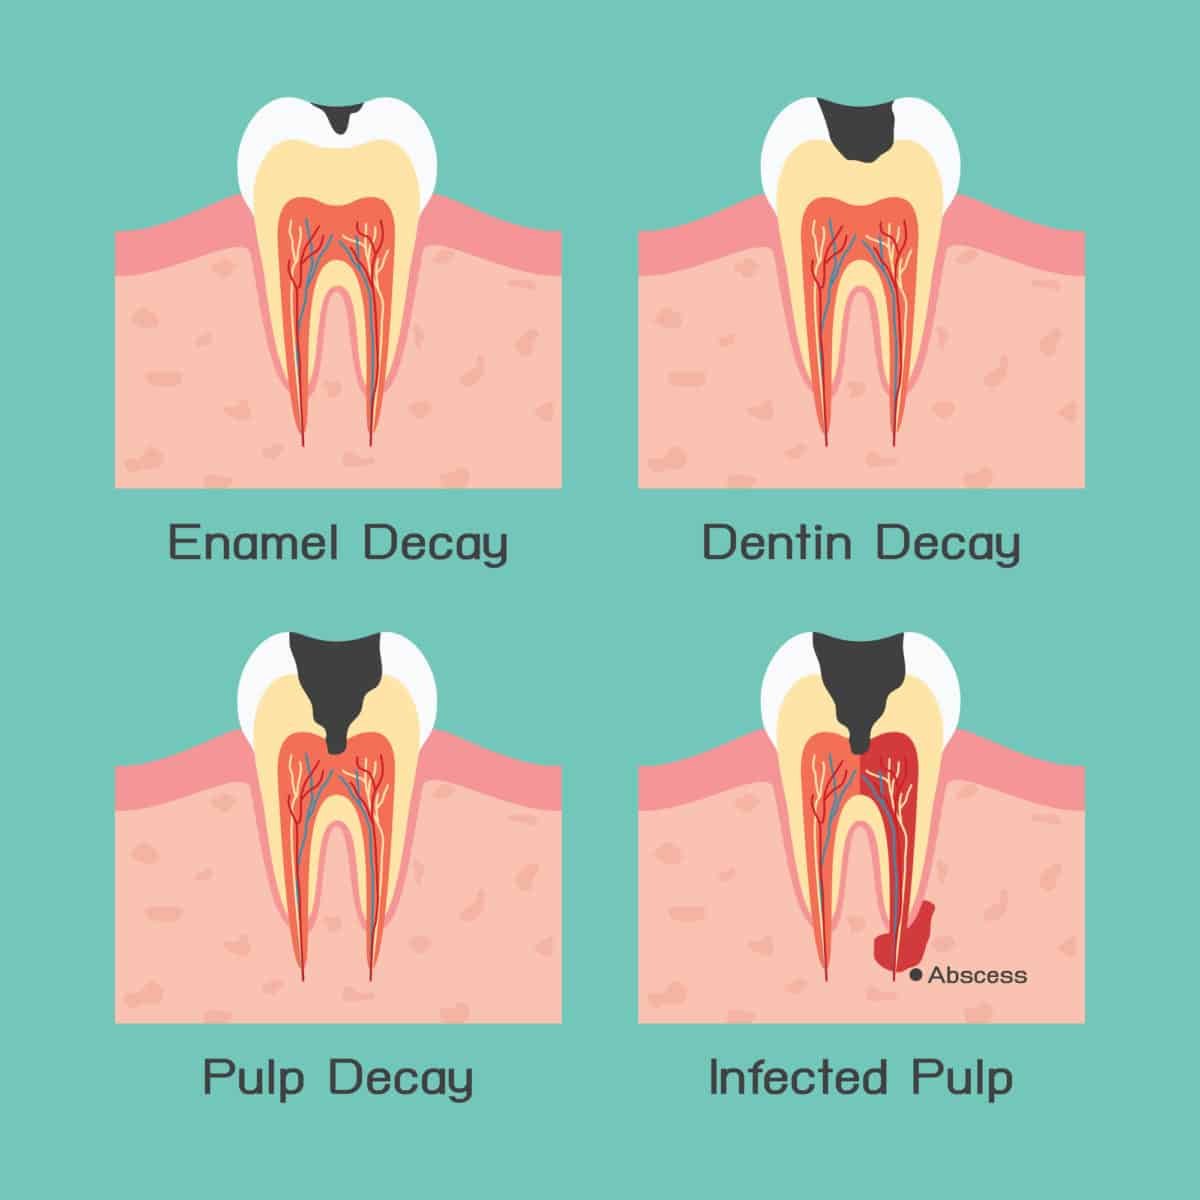

- Inflammation and Infection: When decay reaches the pulp (the innermost part of the tooth containing nerves and blood vessels), it can cause inflammation (pulpitis) or even an infection leading to an abscess. This inflammation or infection puts pressure on surrounding nerves, and the pain can radiate upwards to your head.

- Referred Pain: Our brains can sometimes get confused about where pain is coming from. Pain originating in a decayed tooth can be "referred" to other areas of the head, such as the temples, forehead, or even around the eye. This means the actual source of the pain is the tooth, but you feel it elsewhere.